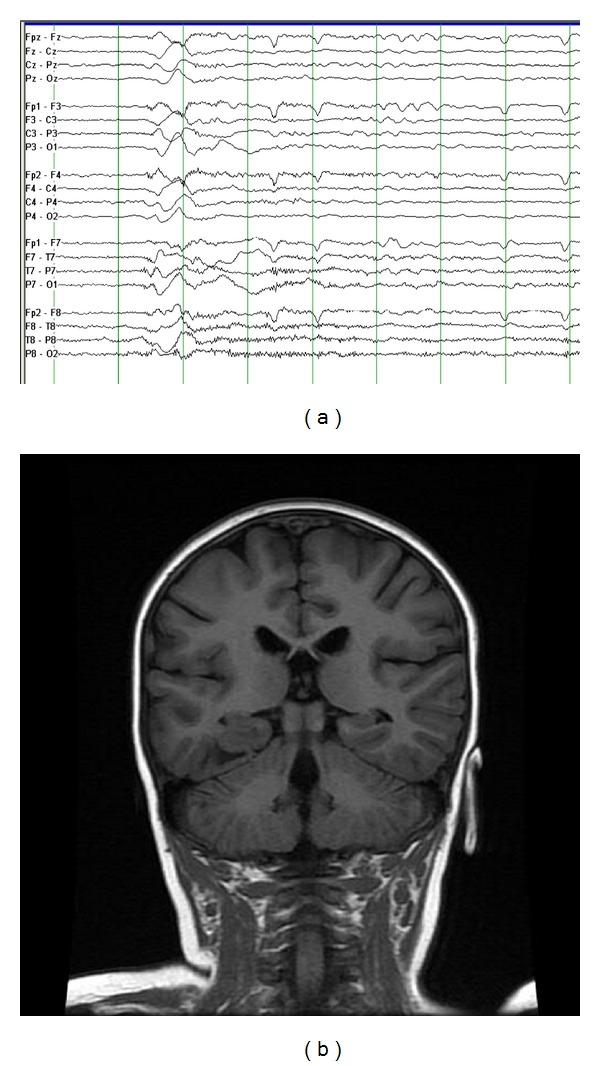

The temporal lobe is a common focus for epilepsy. Temporal lobe epilepsy in infants and children differs from the relatively homogeneous syndrome seen in adults in several important clinical and pathological ways. Seizure semiology varies by age, and the ictal EEG pattern may be less clear cut than what is seen in adults. Additionally, the occurrence of intractable seizures in the developing brain may impact neurocognitive function remote from the temporal area. While many children will respond favorably to medical therapy, those with focal imaging abnormalities including cortical dysplasia, hippocampal sclerosis, or low-grade tumors are likely to be intractable. Expedient workup and surgical intervention in these medically intractable cases are needed to maximize long-term developmental outcome.

颞叶是癫痫的常见病灶。婴幼儿颞叶癫痫在临床和病理的几个重要方面与成人相对单一的综合征有所不同。发作症状学因年龄而异,发作期脑电图模式可能不如成人那样清晰明确。此外,发育中大脑顽固性癫痫发作的发生可能会影响颞叶区域以外的神经认知功能。虽然许多儿童对药物治疗反应良好,但那些有局灶性影像学异常,包括皮质发育异常、海马硬化或低度肿瘤的儿童很可能难以治愈。对于这些药物治疗无效的病例,需要进行及时的检查和手术干预,以最大限度地提高长期发育结果。